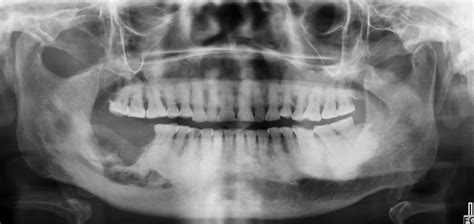

2. Pérdida Ósea Dental

La pérdida ósea dental se refiere al deterioro o disminución de la masa ósea que rodea y sostiene los dientes.

Este hueso alveolar es esencial para mantener los dientes firmes en su lugar y proporcionar un soporte adecuado para masticar y hablar. Cuando se pierde masa ósea en esta zona, los dientes pueden comenzar a moverse, lo que lleva a problemas de estabilidad y funcionalidad en la boca.

Puede desencadenarse por diversas causas, y entre las más importantes están la pérdida de piezas dentales o infecciones en la boca.

El hueso dental o alveolar es aquel que aloja y sostiene los dientes para que puedan realizar la función de masticación. Este hueso mantiene su forma y tamaño gracias a la presión que ejercemos al masticar y morder, ya que transmitimos un estímulo imprescindible para su conservación.

La pérdida ósea del hueso alveolar tanto de la mandíbula como del maxilar superior es una consecuencia común de la periodontitis crónica y de la pérdida de dientes. La causa más común de pérdida ósea es la pérdida de dientes que no se reemplazan, especialmente cuando son varios dientes seguidos.

Cuando se extraen dientes, el hueso se reabsorbe. El hueso alveolar forma las crestas en las que están incrustados los dientes.